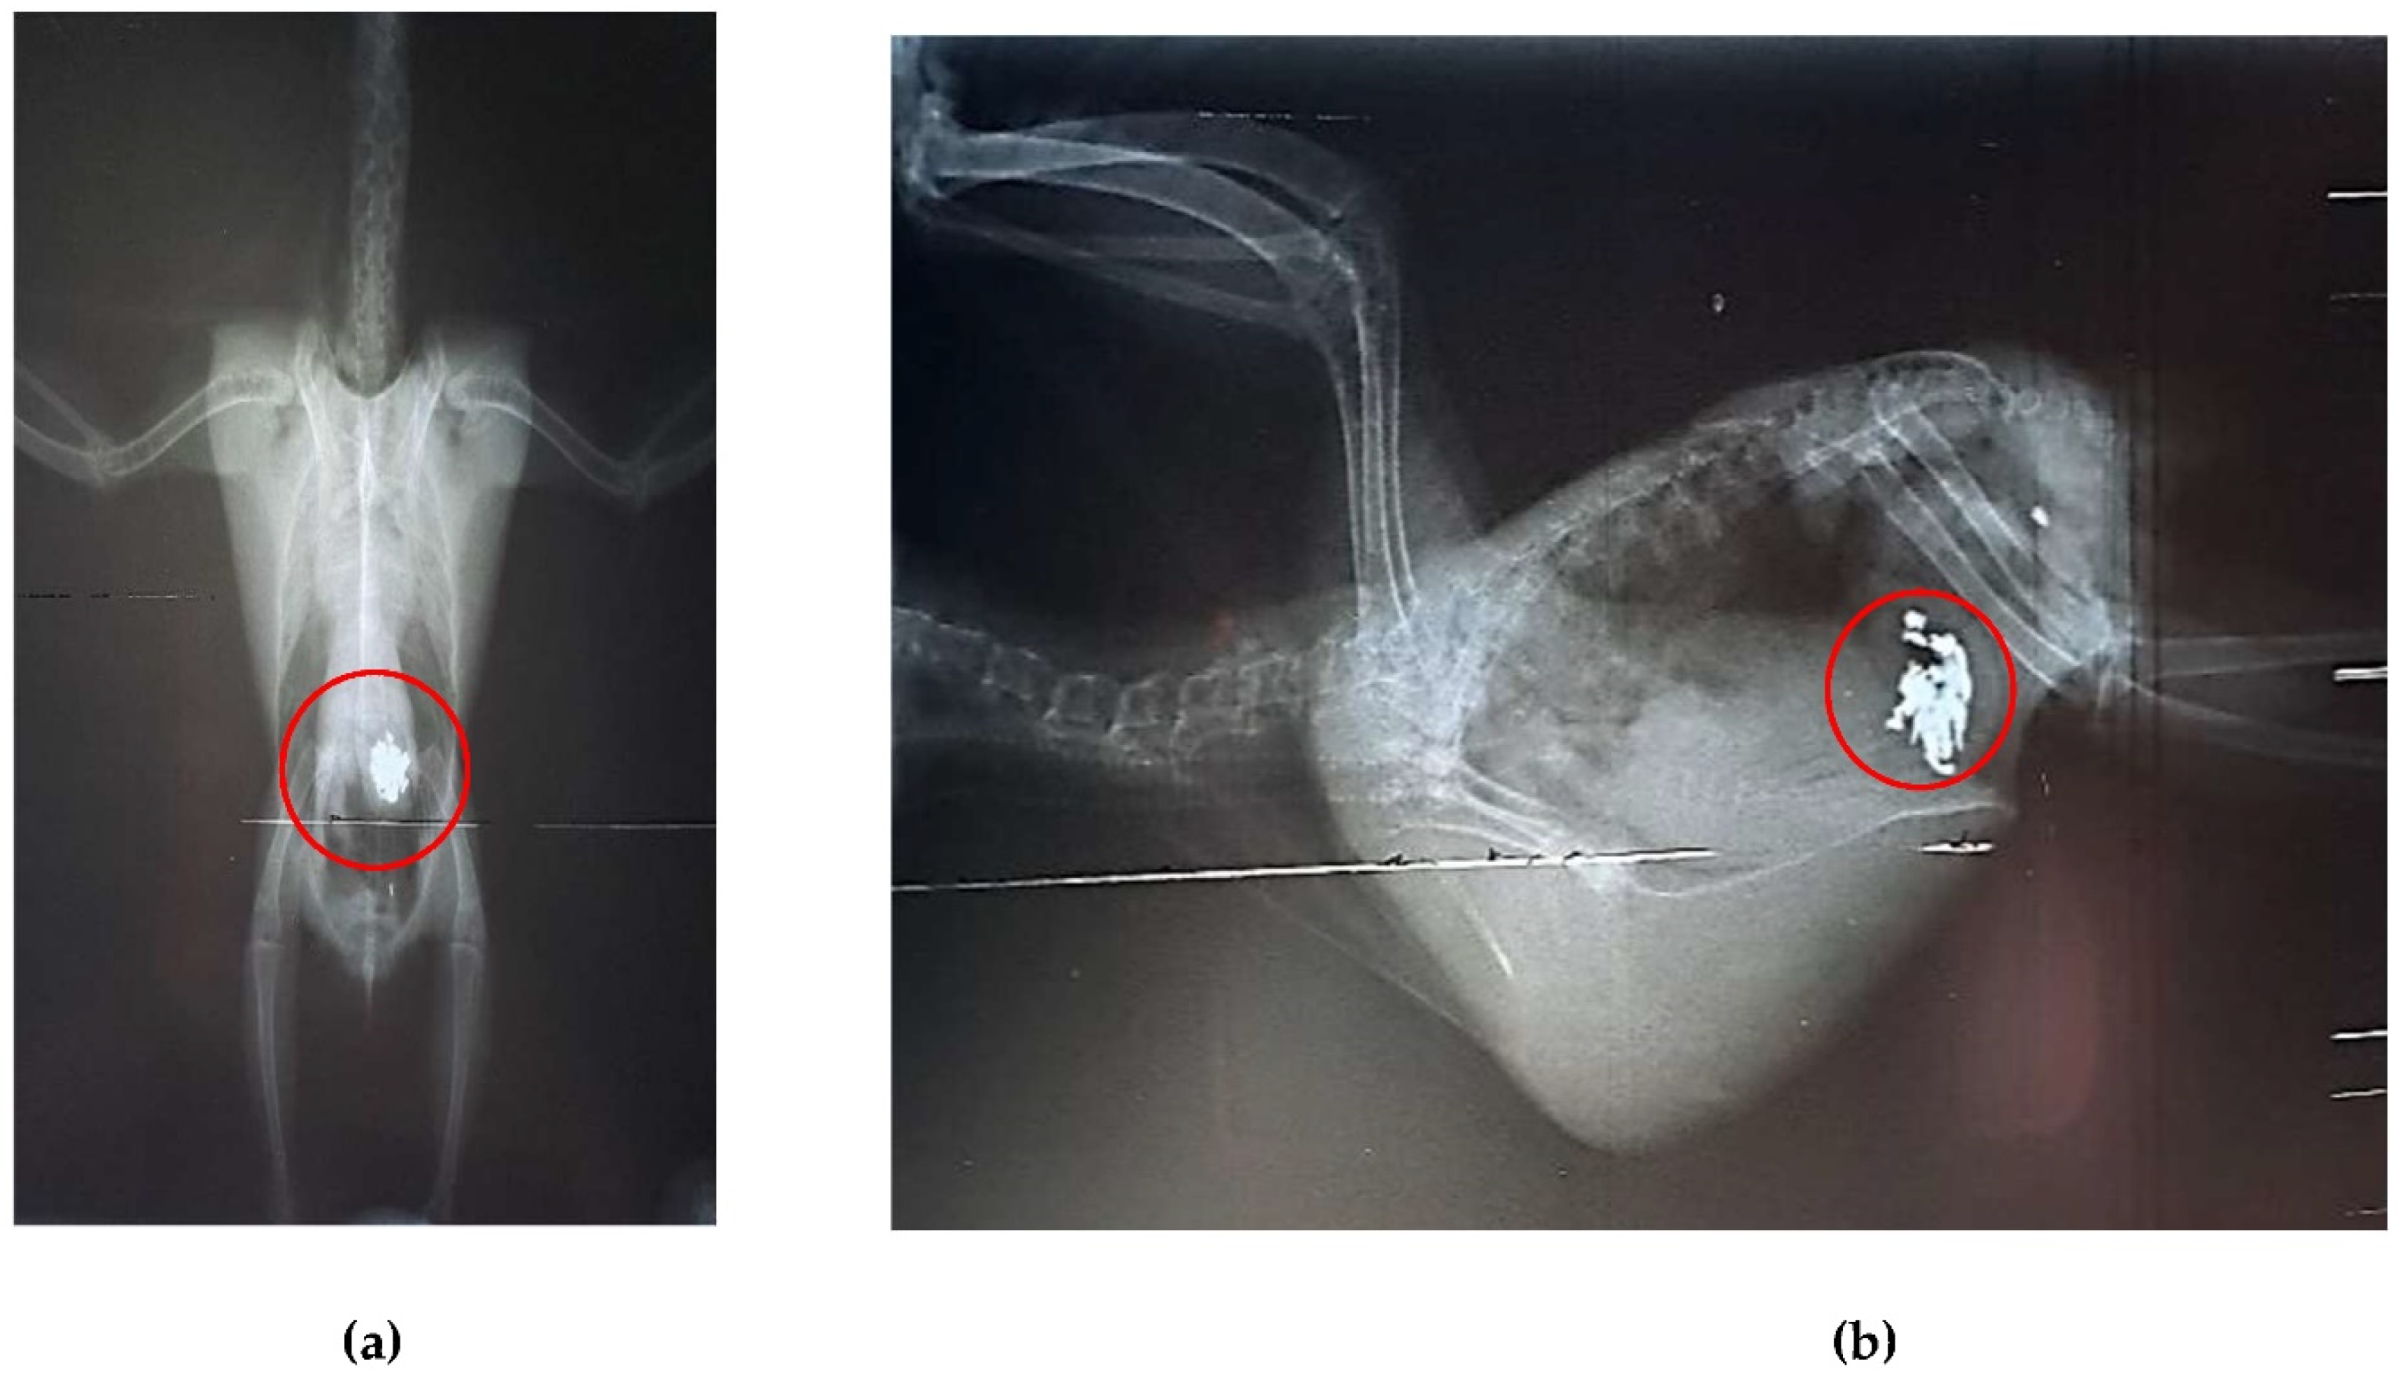

Radiographic examinations revealed a significant accumulation of radiopaque foreign bodies in the ventriculus of both birds, suggestive of metal ingestion (Figure 3A, B and Figure 4A, B). The hematological results are presented in Table 1.

Figure 3. Radiographic examination of the coelomic cavity of Arantiga jandaya (bird 1). (a) Ventrodorsal projection – The heart and liver form a typical hourglass-shaped structure, with pulmonary field radiopacity; dilated ventriculus and proventriculus; radiopaque structures (outlined in red) in the ventriculus region, suggestive of metal content. (b) Right laterolateral projection – Presence of radiopaque foreign bodies (outlined in red), also suggestive of metal.